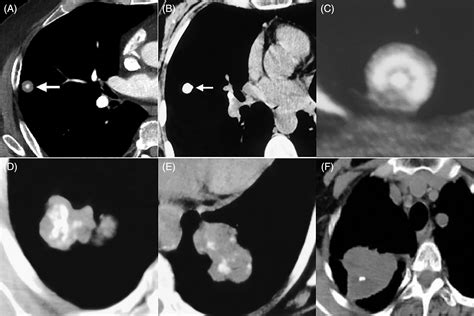

• Chest X-ray: A chest X-ray can reveal the presence of calcium deposits in the lungs.

• CT Scan: A computed tomography (CT) scan provides detailed images of the lungs and can help identify the location and extent of the calcification.

• Tumors: Both benign and malignant tumors can cause calcification in the lungs.